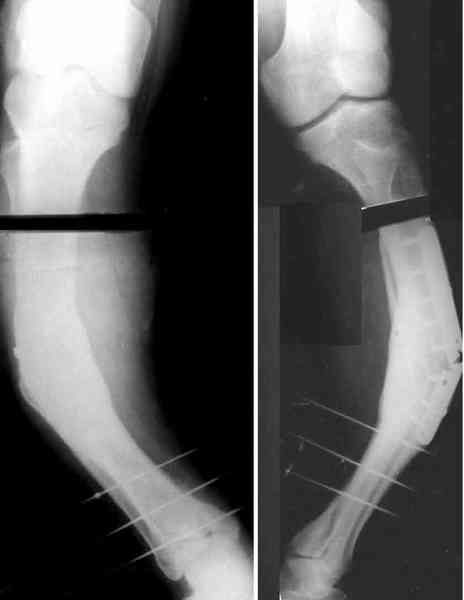

Для продолжения темы - несколько картинок.

Пациент 30 лет, лет пять назад оперирован по поводу перелома голени пластиной. Находясь на героине, нарушил режим, пошел, сломал и ногу и

пластину, но перелом сросся.

В приложении - внешний вид и рентген.

Мнения?

Лукавить не буду, я его уже вылечил. Но применил немного необычную тактику по отношению к пластине - результат после обсуждения...

Александр, как раз уровень остеотомии подробнее - на вершине деформации? Там Сломанная пластина.

Там не винты (может, плохо видно), а сломанная пластина, вросшая в кость.

Ну, например, на уровне перелома пластинки. Можно пересечь часть кости, не прилежащую к пластинке, затем надломить остальное.

a> Там не винты (может, плохо видно), а сломанная пластина, вросшая в

a> кость.

Пластинку и винты мне удалось разглядеть только на профильной проекции, точнее, трехчетвертной, судя по виду коленного сустава (правый снимок). На фасной - вообще не могу разобрать, где она :( Но, в конце концов, можно и не видя ее сказать, что уровень остеотомии может быть и другим, ниже или выше пластинки, придется только компенсировать смещение по ширине, которое появится при полном устранении угла не на вершине.